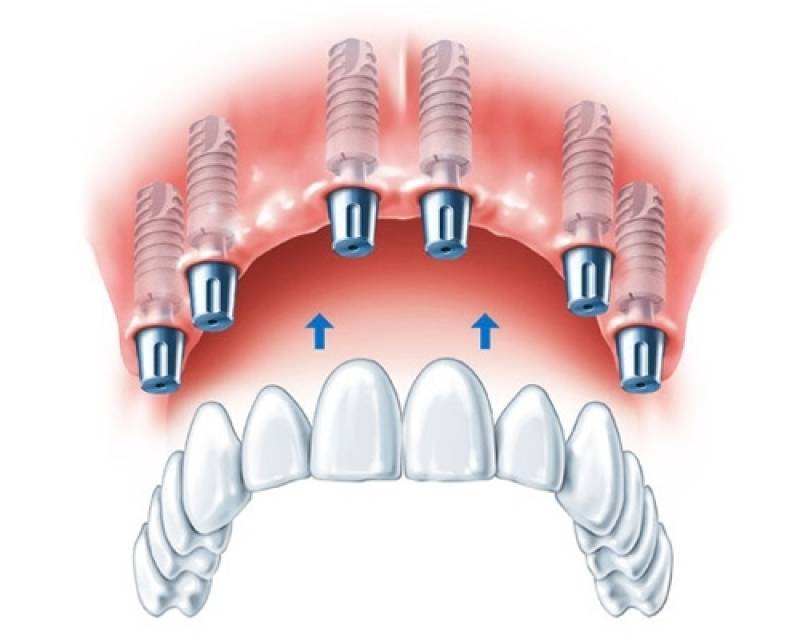

Implante dentário é formado por um cilindro (pino) de titânio, que é inserido dentro do osso, abaixo da gengiva. O tamanho do cilindro varia entre 3 e 6 mm de diâmetro. O titânio, metal biologicamente compatível que se integra perfeitamente ao osso, tem a peculiaridade de impedir qualquer tipo de rejeição óssea. Dessa forma, o implante dentário faz o papel da raiz do dente. Sobre os implantes é que são colocadas as próteses em metalocerâmica, que é o material mais semelhante ao dente natural.